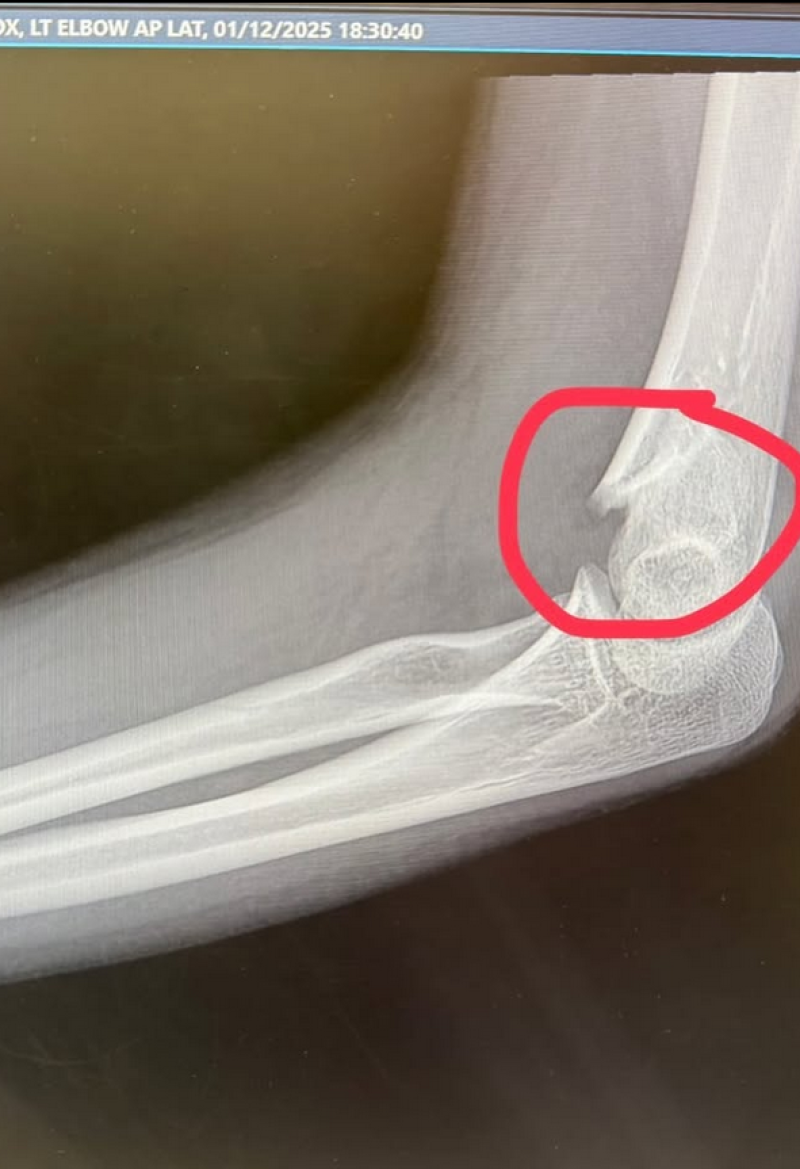

เรียกได้ว่าเป็นอีกหนึ่งนักแสดงสาวมากความสามารถสำหรับ น้องอินเตอร์ ที่ล่าสุดได้เกิดอุบัติเหตุขณะซ้อมเต้น จนแขนหัก โดยเล่าว่า อุบัติเหตุเกิดขึ้นได้ทุกเวลา มาเรียนเต้นแต่ลื่นล้ม แขนหัก เศร้าเลยค่ะ ขอโทษกองละครทุกกองด้วยค่ะ จะรีบหายไวไวนะคะ

และขอบคุณครูจ๋าครูฝ้ายที่อุ้มมาส่งขึ้นรถ ตอนนี้รอผ่าตัด ดามเหล็ก ขอบคุณทุกคนที่เป็นห่วง ส่งกำลังใจมาให้น้องอินเตอร์นะคะ ท่ามกลางพี่ๆในวงการต่างเข้ามาคอมเมนต์ส่งกำลังใจกันอย่างมาก